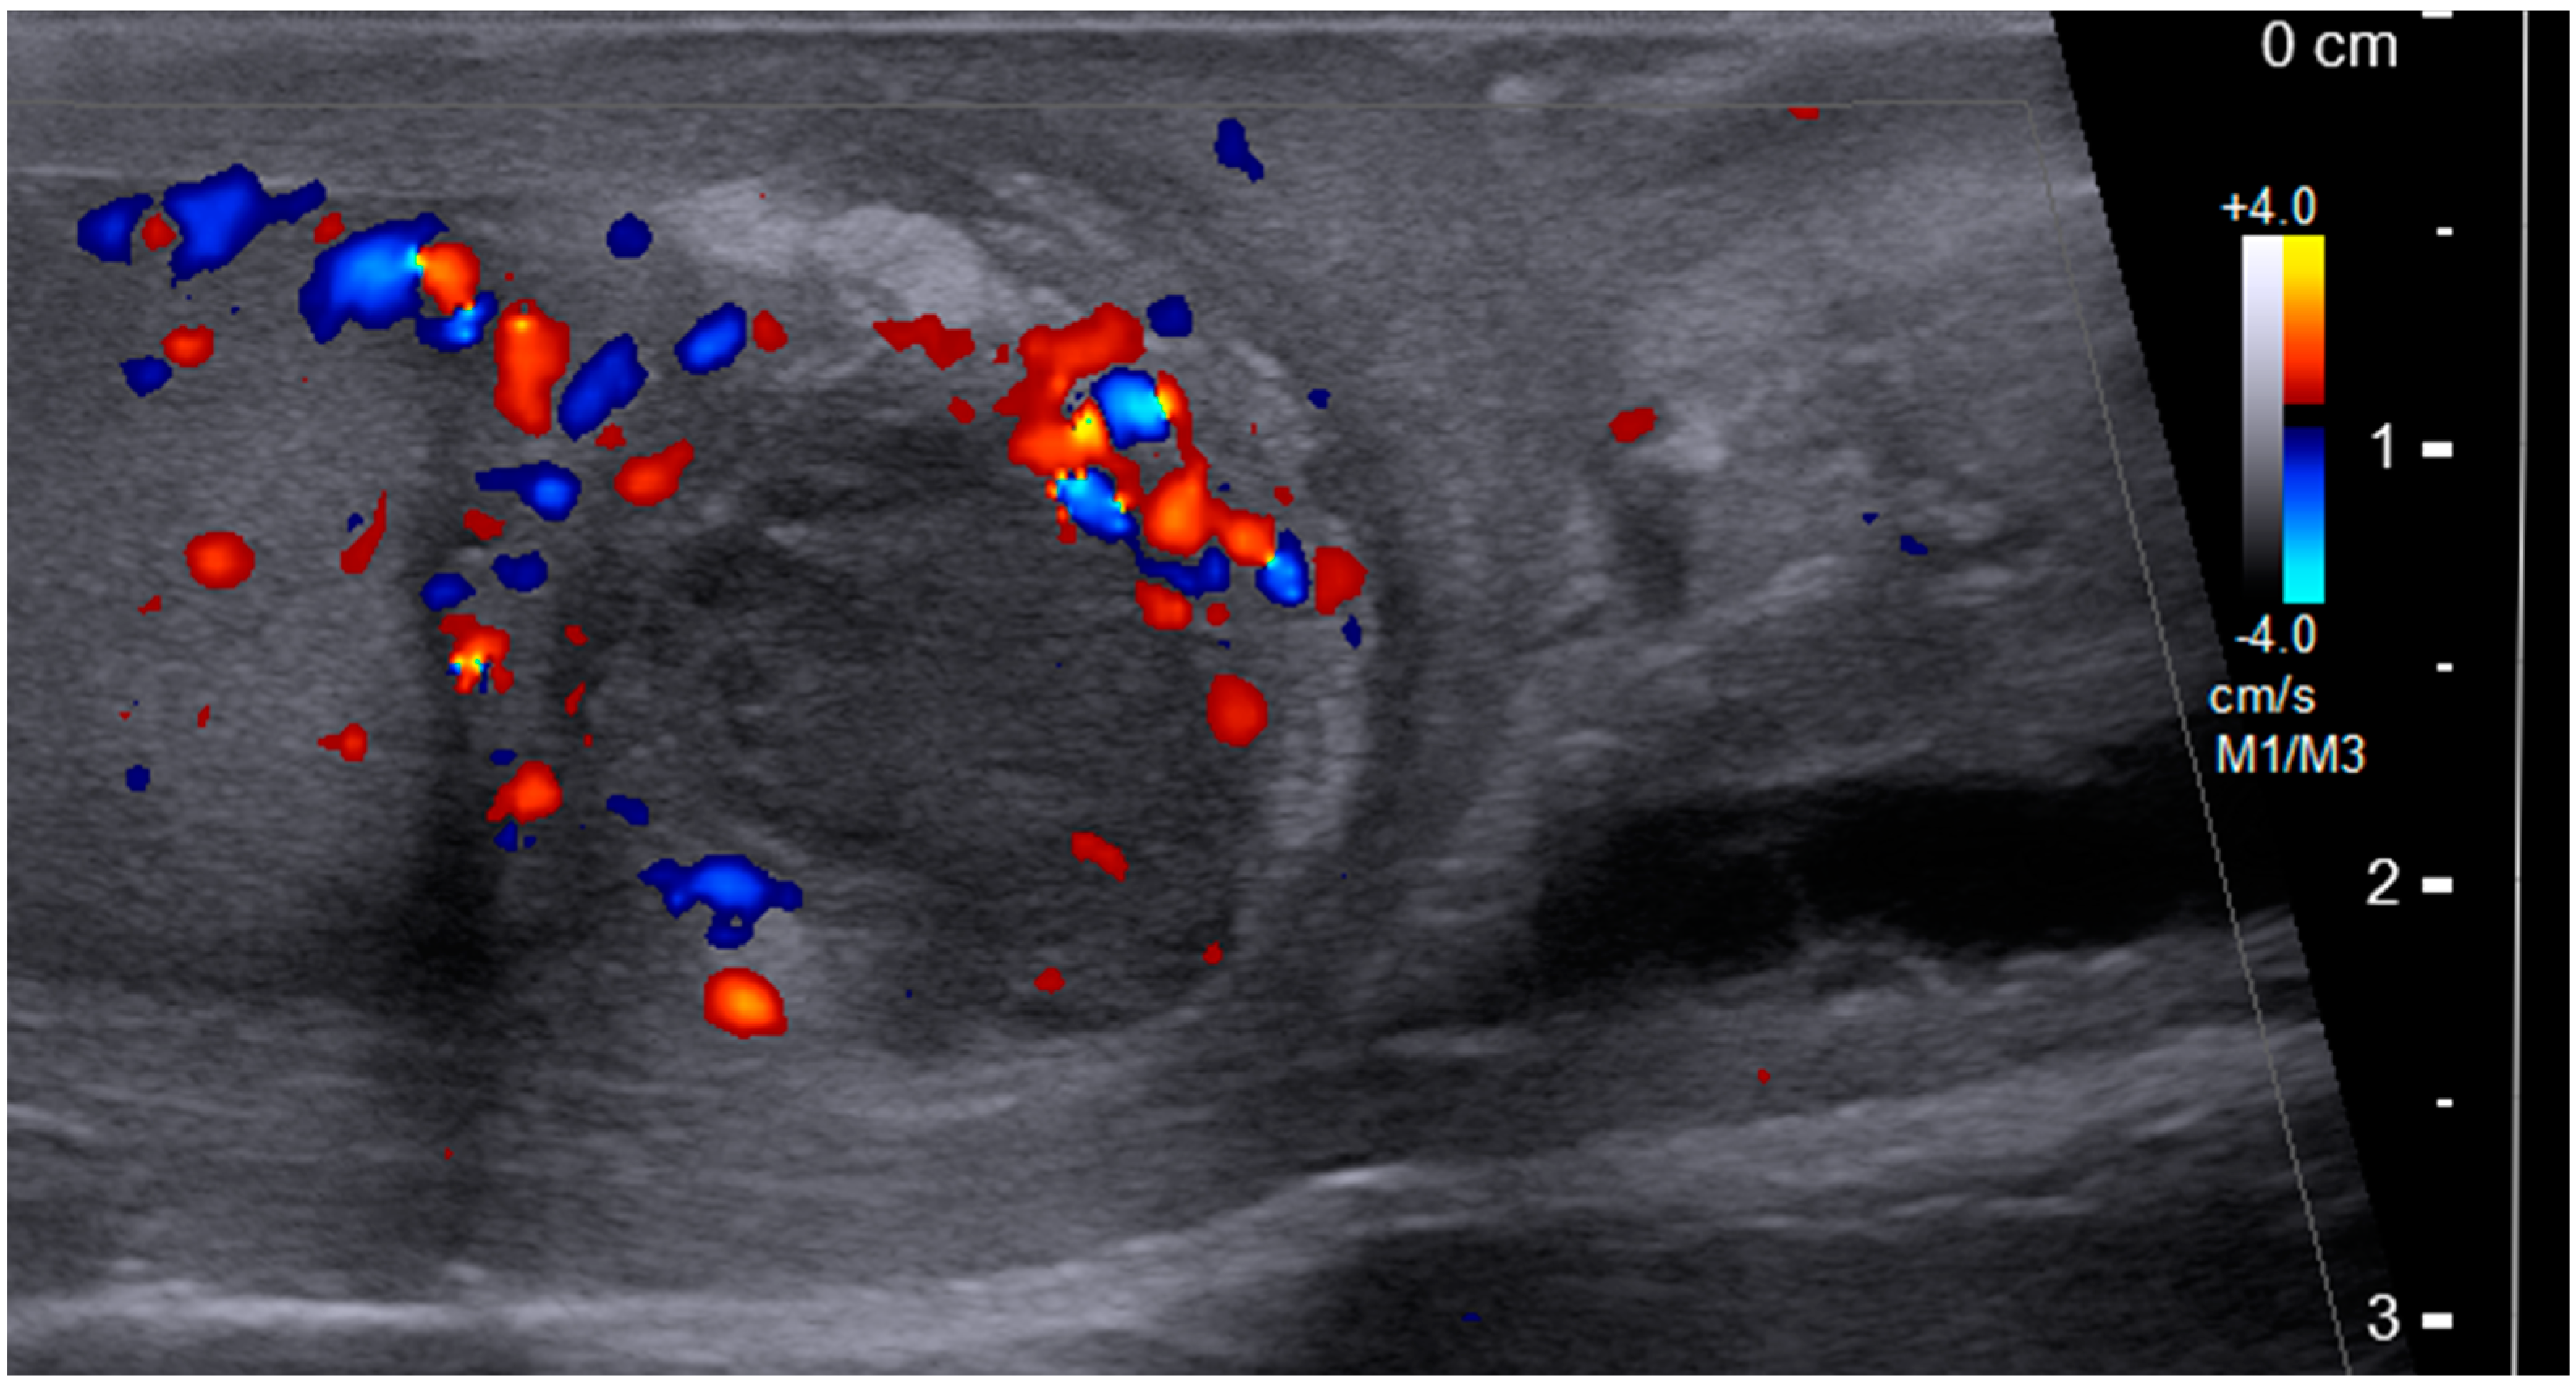

2. Case Presentation